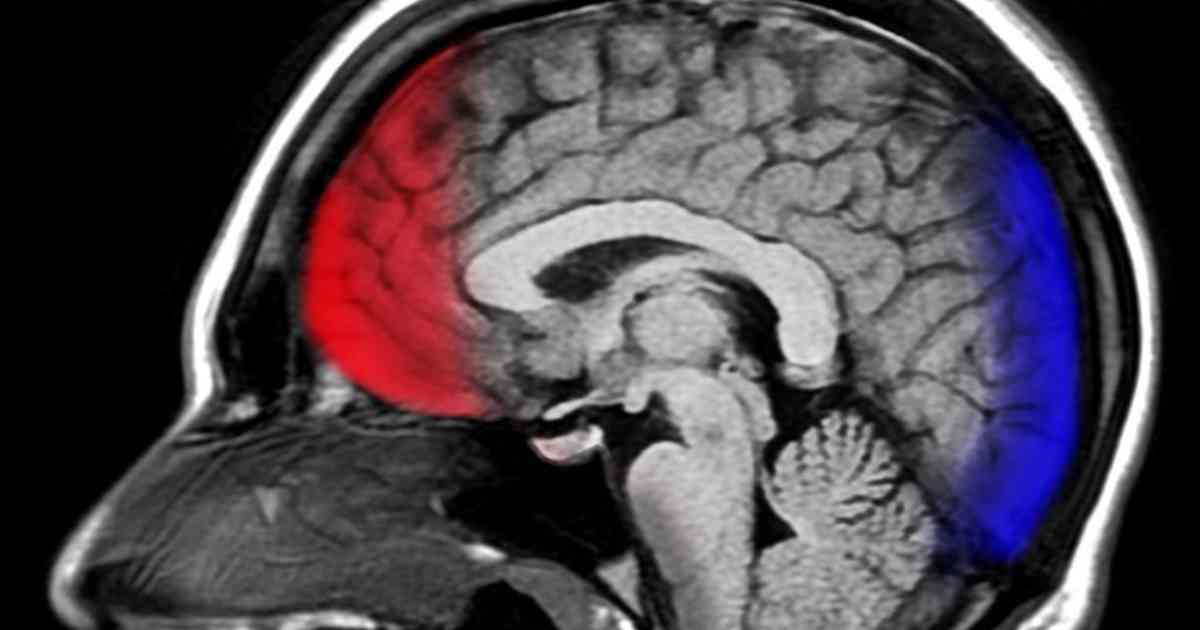

Neuroscientists have found that if you really feel it when you say it, you'll be happier and healthier. The regular practice of expressing gratitude is not a New Age fad; it's a facet of the human condition that reaps true benefits to those who mean it.